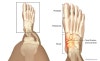

부주상골(Accessory navicular)와 감별이 중요합니다.

1. Dorsal avulsion fracture(50%)

2. Tuberosity fracture(20~25%)

- Body’s fracture : 추락이나 direct blow에 의해 압박골절 유발